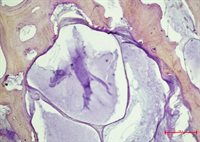

A new method for measuring bone marrow lesions for pain research in people with osteoarthritis

Within the bones of people with osteoarthritis there are often regions called Bone Marrow Lesions (BMLs) which are seen using MRI scanners. They appear to be linked to inflammation and pain. When BMLs are close to the knee joint, they appear to be closely related to osteoarthritis knee pain. Joint tissues are very useful for research aiming to characterise cells and molecules that might be targeted by new drugs in order to relieve pain.

For more details, visit the summary page